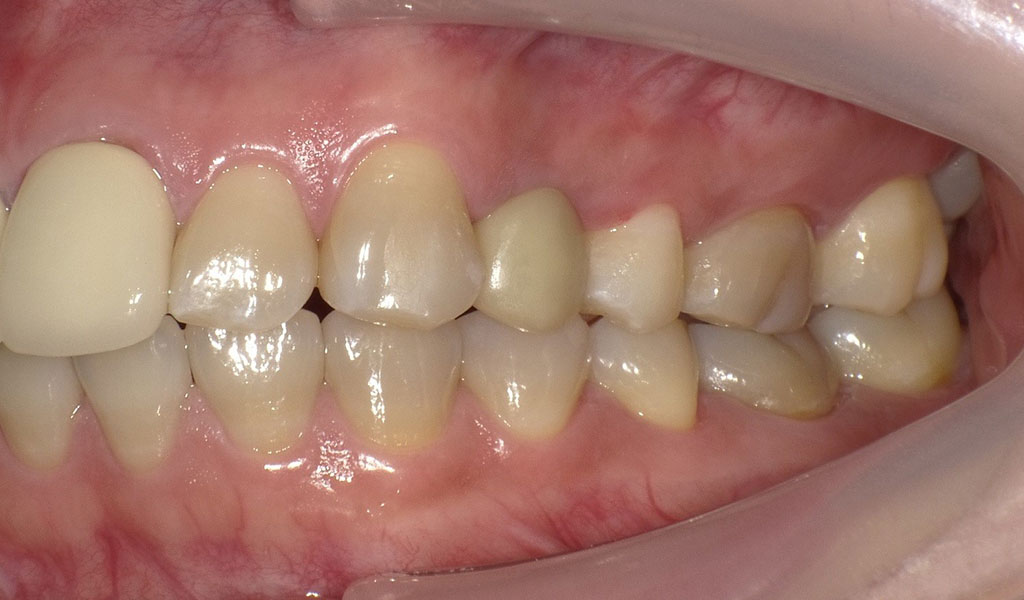

30代女性・横浜市在住。左上4番の詰め物の奥に虫歯ができてしまい、脱離。他院にて相談したがセカンドオピニオンとして当院を受診。当院にて左上4番を抜歯後、インプラント治療。人工歯はジルコニア人工歯。スクリューリテインにて固定しました。

Before2

After2

左上4番インプラント治療

左上4番を抜歯後、通常手術にて、左上4番の骨に即時にインプラントを埋め込みました。

インプラントと骨がしっかり結合するまで術後3ヶ月待ち、インプラントの上に人工の歯を被せる治療を行いました。